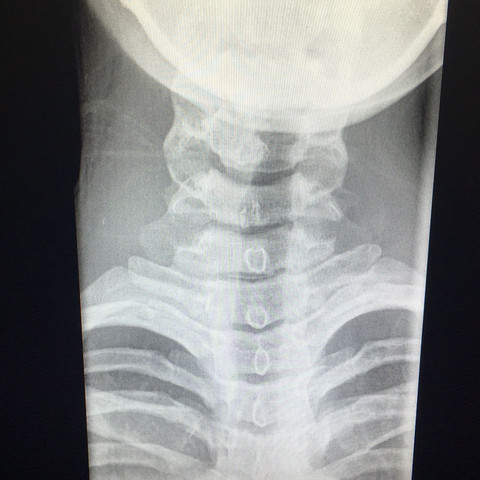

Post Unfall Zustand Mit Spondylose Osteophyten Und Fraktur Der Halswirbelsaule C3 4 C4 5 C5 6 C6 7 Stockfotografie Alamy

Halswirbelsaule Rontgenaufnahmen Was Stimmt Da Nicht